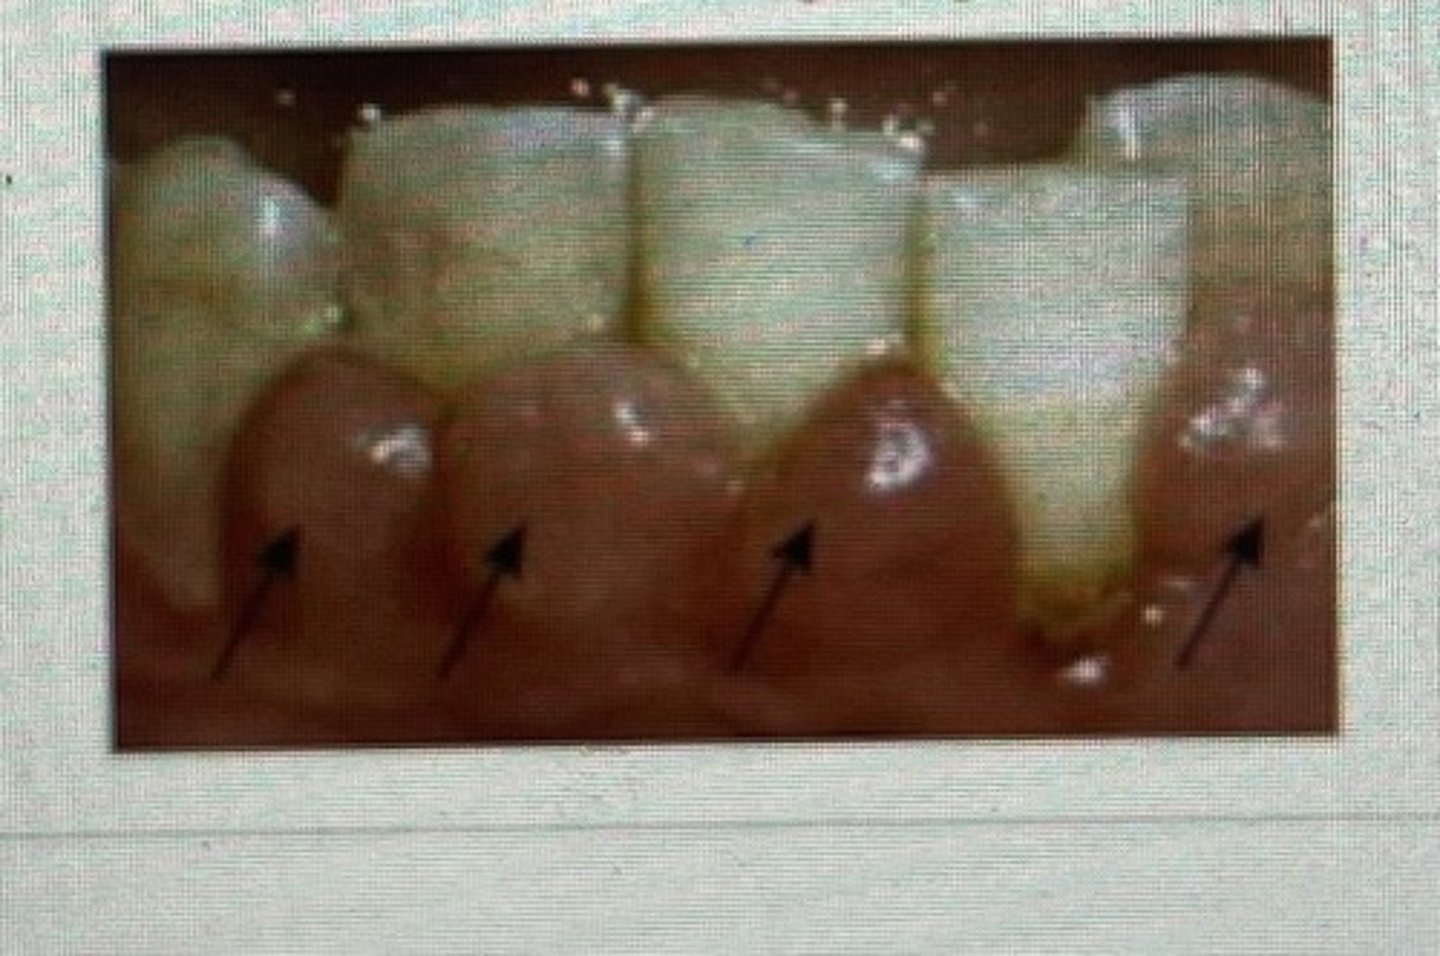

Method/technique: Bristles are directed apically at 45 degrees (up for maxillary and down for mandibular) to long axis of tooth, mostly it is difficult to place at 45 degrees so placing parallel to teeth is also beneficial

Now press the bristles slightly so that they enter the gingival sulcus and embrasures.

Vibrate the brush back and forth with short strokes for 10-15 strokes for each position and move to the next teeth